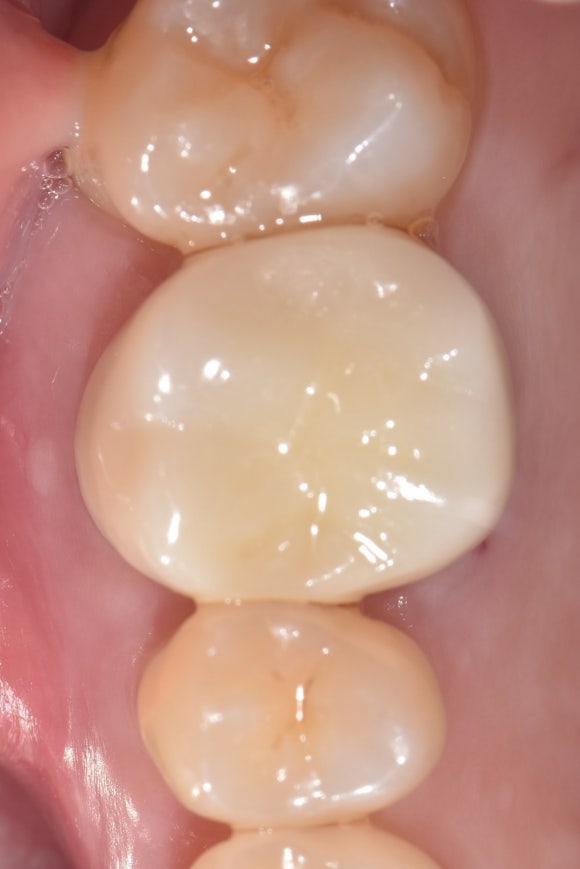

20240930

신경치료의 마무리는 튼튼한 크라운입니다.

크라운으로 씹는 면을 확실히 보호해주어야

치아 내부가 다시 감염되거나

파절되는 일을 방지할 수 있습니다.